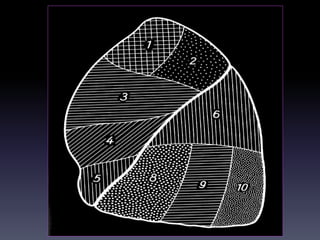

CAÂY PHEÁ QUAÛN VAØ PHAÂN

THUØY PHOÅI

+CT cho chi tieát giaûi phaãu toát raát nhieàu so

vôùi X quang qui öôùc

+Phaân tích hình aûnh CT

-Caây pheá quaûn

-Phaân thuøy phoåi

-Raõnh maøng phoåi